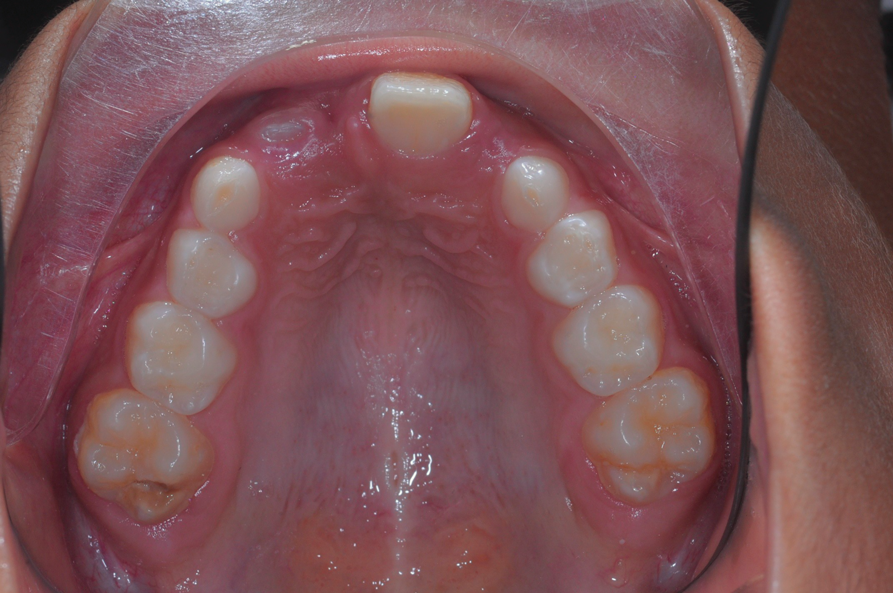

The following case illustrates the complete surgical/orthodontic treatment sequence for an impacted maxillary right central incisor. An 8½-year-old patient presented with a chief complaint of crowded teeth. The maxillary left central incisor was the only erupted incisor at the time of consultation (Figure 2 and Figure 3). Crowding was clinically diagnosed visually by the prominence of the unerupted right central incisor in the vestibule, and this was confirmed with a panoramic radiograph (Figure 4).

Fig 2. Initial situation of case involving an impacted maxillary right central incisor, frontal view (Fig 2) and occlusal view (Fig 3).

Fig 3. Initial situation of case involving an impacted maxillary right central incisor, frontal view (Fig 2) and occlusal view (Fig 3).

Figure 3